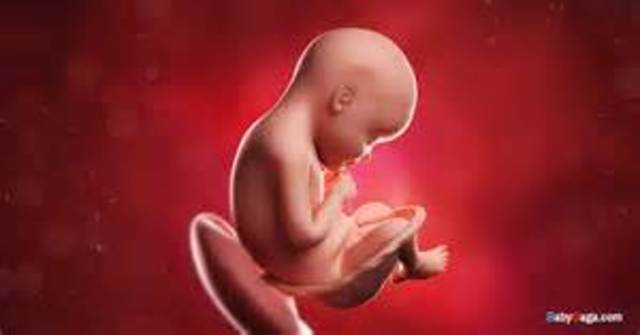

In week ten, the baby becomes a fetus and all of its organs, nerves, and muscles begin to function within its body. During this week of development the fetus is about the size of a strawberry.,

By week thirteen, the baby has grown to about 3 inches and is now able to produce insulin to control its blood glucose.